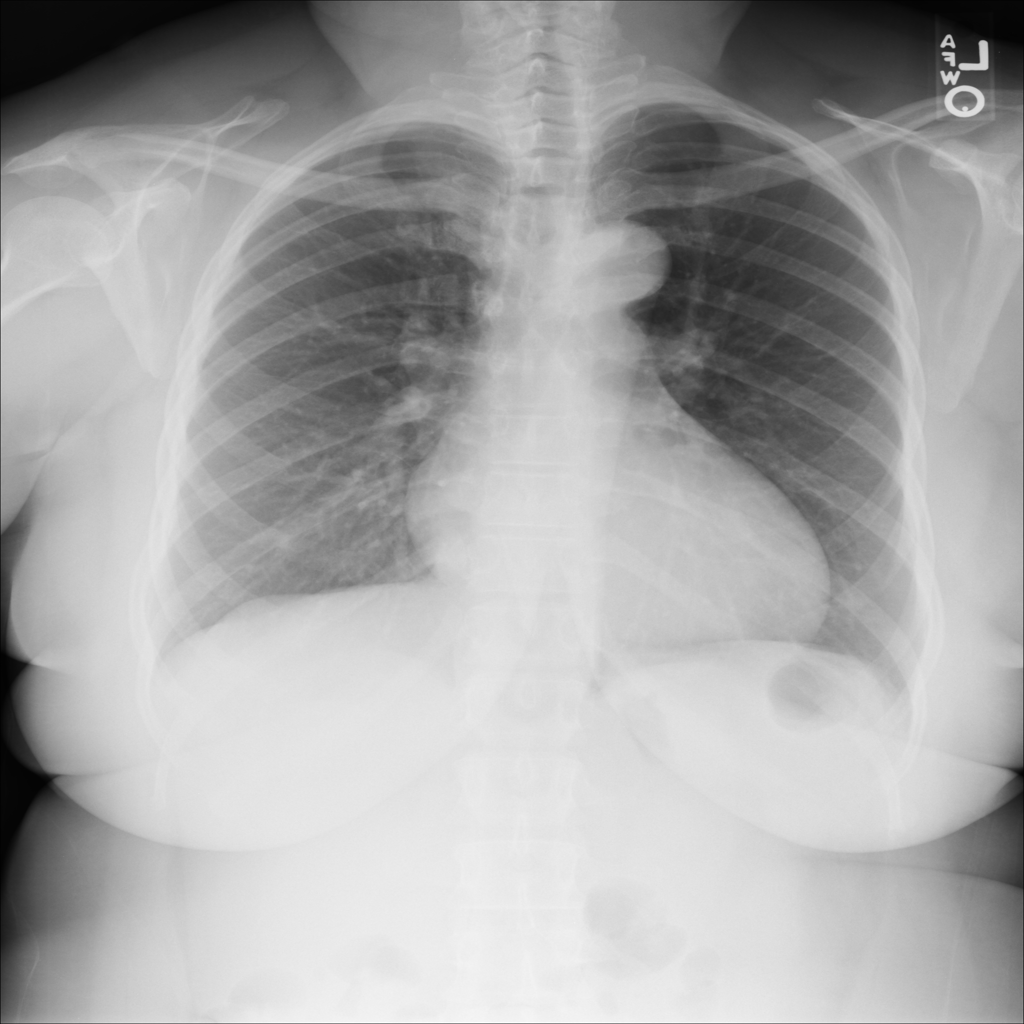

PAT-AE5C · IMG-000Cardiomegaly

PAT-AE5C · IMG-000

PA